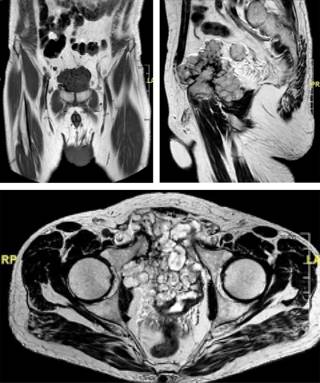

Ante la discordancia en los informes de las pruebas diagnósticas se completa el estudio con una resonancia magnética nuclear (RMN), que informa de «tumoración pélvica de 10 cm de diámetro mayor con origen en la rama iliopúbica derecha que por sus características es compatible con un condrosarcoma que infiltra la pared anterior de la vejiga y el músculo obturador interno derecho» (Figuras 4 y 5).

Figura 5: Cortes STIR de resonancia magnética nuclear anteroposterior y axial. STIR: Short Tau Inversion Recovery.